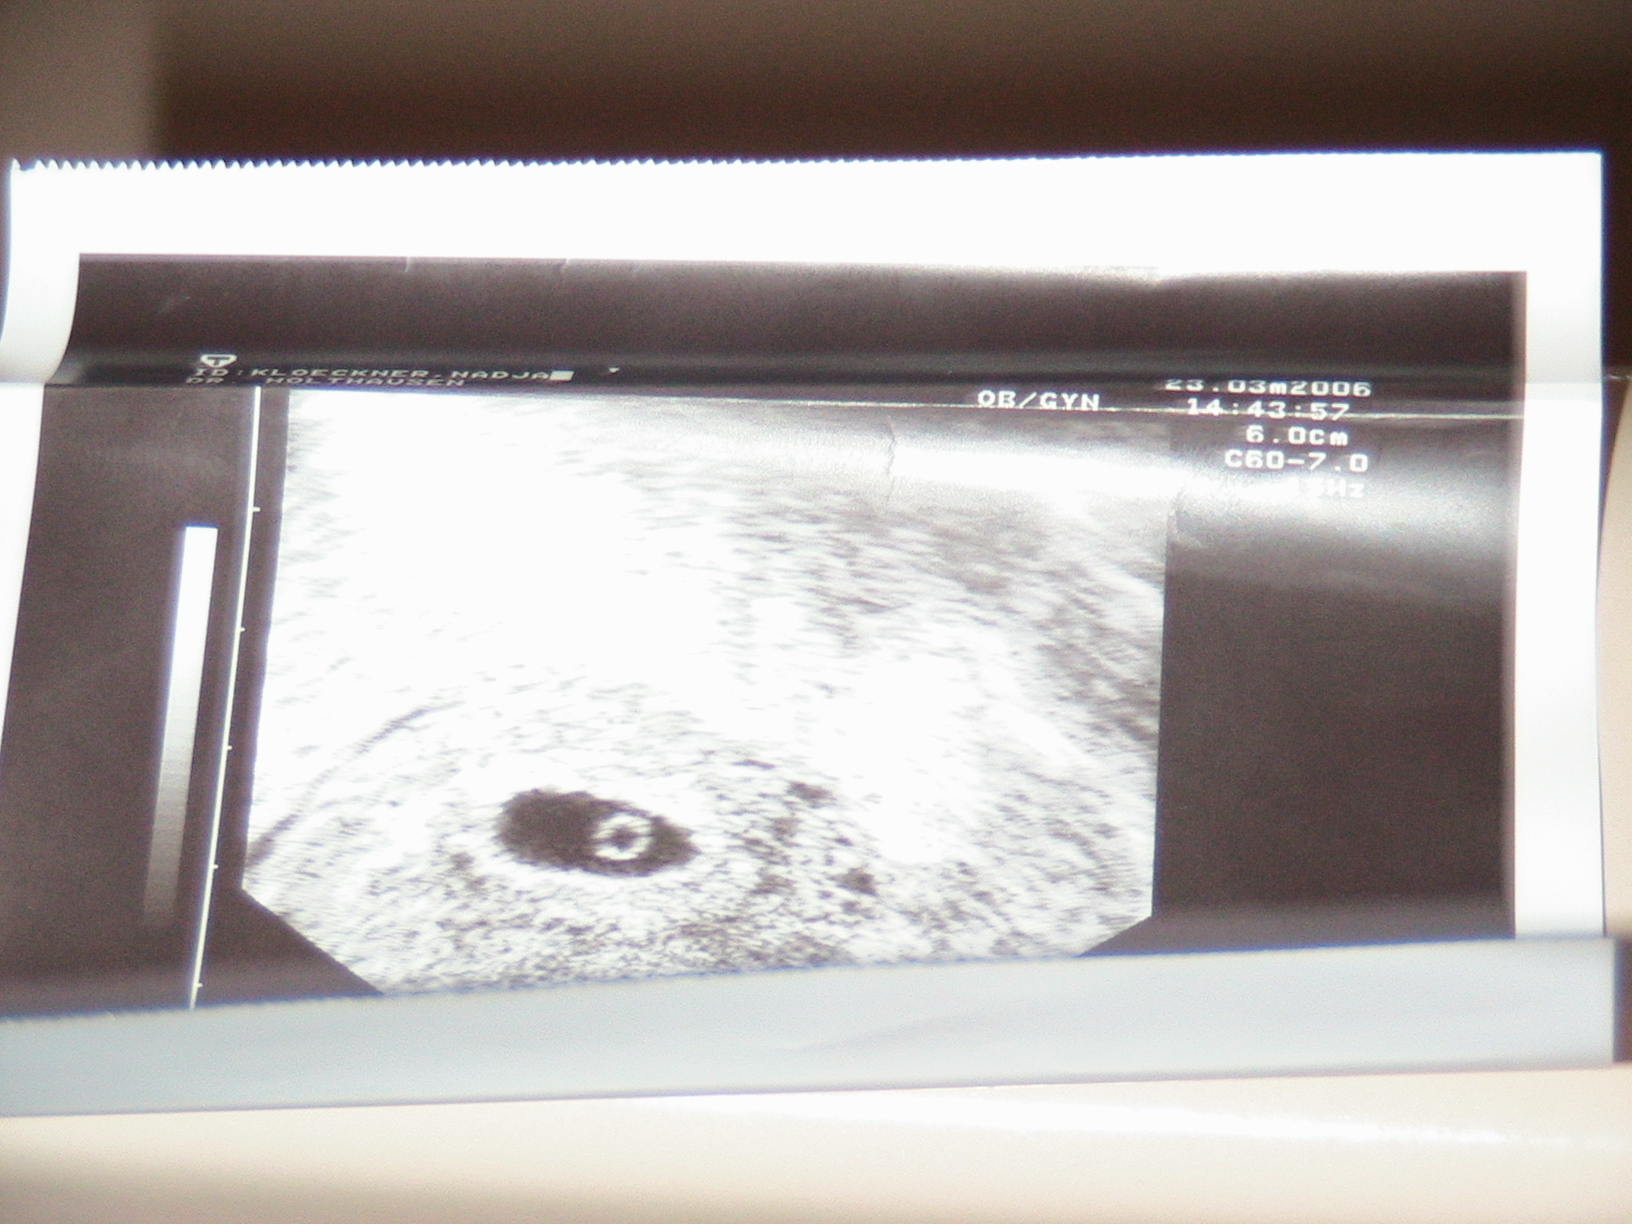

So hier bin ich also die Fruchhöhle ist richtig gut gewachsen dort drin beFindet sich auch schon ein Fruchtsack aber leider noch kein Embroy in sicht jetzt muss ich wieder in einer Woche zum ARZT :knuddel:

So hier bin ich also die Fruchhöhle ist richtig gut gewachsen dort drin beFindet sich auch schon ein Fruchtsack aber leider noch kein Embryo jetzt muss ich wieder in einer Woche zum ARZT :knuddel: Aber mein Doc war heute so komisch und ich finde das das Bild so komisch aussieht.

Bild 002.jpg

wurde denn nochmal der HCG Wert abgenommen ??? Normalerweise wird dieser ständig kontrolliert, solange noch kein schlagendes Herzchen in sicht ist. So war es jedenfalls bei mir immer. Vielleicht ist das Gerät ja auch nicht das beste, was dein Doc hat und nächste Woche ist dann alles o.k. Und wenn Du Dir zu unsicher bist, geh einfach gleich anfang nächster Woche zur Kontrolle nchmal hin. Denn es ist weder gut für Dich noch für das Krümelchen, wenn Du dir zu viele Sorgen machst :knuddel: Ich suche nachher nochmal meine Bilder raus, aber ich glaube bei mir sah das um diese Zeit auch noh nicht anders aus. Warum meinst Du das dein Doc heute komisch war ??? Was hat er denn genau gesagt beim US ???

Der Doc hat mir noch kein Blut abgenommen das wurde nur im Krankenhaus gemacht ich warte einfach mal bis nächste Woche Donnerstag ab dann werde ich es ja sehen.der Dottersack ist doch normall Ovall oder?

Ich meinte das der Arzt so komisch war denn normal nimmt man doch blut ab er will es aber erst nächste Woche machen eigentlich finde ich denn Arzt total in Ordnung aber es kan ja auch sein weil meine Gefühle Momentan durch und durch gehen :knuddel:

die Form des Dottersacks ist eigentlich egal. Habe damals aber diesbezüglich auch Dr. Peet gefragt. Man reagiert, ja auf alles viel empfindlicher als sonst, aber das ist ja eigentlich ein gutes Zeichen, wenn die Hormone so zuverlässig sind :D

Ich habe auch Dr Peet gefragt er sagte mir nächste Woche sieht mal Schlumpi :lol: